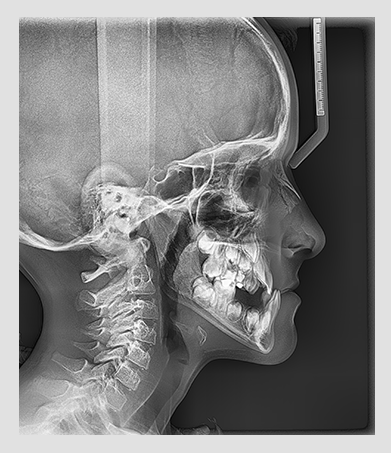

The PaX-i provides optimal images exclusively designed for orthodontics.

There are two image sizes available (lateral and full lateral) that

allow you to choose your image size based on your diagnostic needs.

Provide specialized high-quality images to suit

orthodontics and maxillofacial surgeries.

| EXAMINATION PROGRAM | SCAN TIME | IMAGE SIZE |

|---|---|---|

| LATERAL | 12.9 sec | 21x23cm (8.3x9.1") |

| FULL LATERAL | 16.9 sec | 27x23cm (10.6x9.1") |